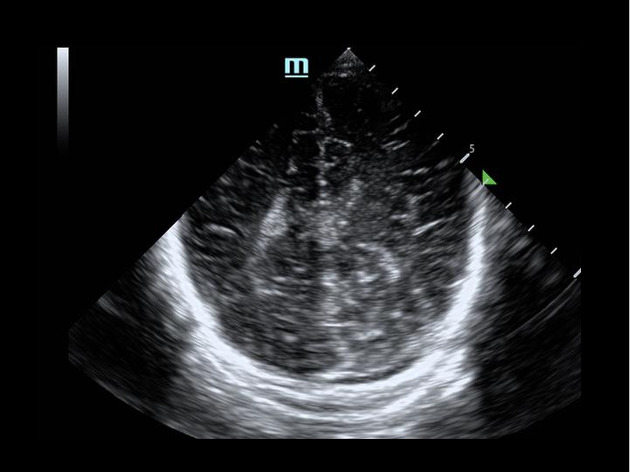

Background: Point of Care Ultrasound (POCUS) is an important tool in pediatric emergency medicine. In neonatal intensive care medicine ultrasound is often used to evaluate the brains of sick neonates. In theory, POCUS could be used in the ED in young children to evaluate the brain for abnormal pathology. Objectives: To examine the ability of PEM faculty to use brain POCUS to identify clinically significant brain injuries in children with head injuries and/or abnormal neurological exams, and generate sensitivity and specificity of brain POCUS in assessing such findings. Methods: This study used a convenience sample of patients seen in a tertiary care pediatric centre who required a CT head. A team of physicians who were trained at a workshop for brain POCUS were on call to perform the POCUS while being blinded to the results of the CT. Results: 21 children were enrolled in the study. Five (24%) of the patients had a CT that was positive for intracranial bleeds. Of the 5 patients with a positive CT, 3 had a brain POCUS scan that was also positive. The two false negative brain POCUS scans were on patients with small bleeds (no surgical intervention required) on CT, as reported by radiology. The sensitivity of brain POCUS was 60% (CI 15% - 95%) with a specificity of 94% (CI 70%-100%). The diagnostic accuracy of brain POCUS was 86% (CI 64% - 97%). Conclusion: This small proof of concept study shows that brain POCUS is an imaging modality with reasonable sensitivity and specificity in identifying intracranial pathologies that are present on CT. Its use may be most beneficial to expedite definitive imaging and subspeciality involvement.

Abstract Image